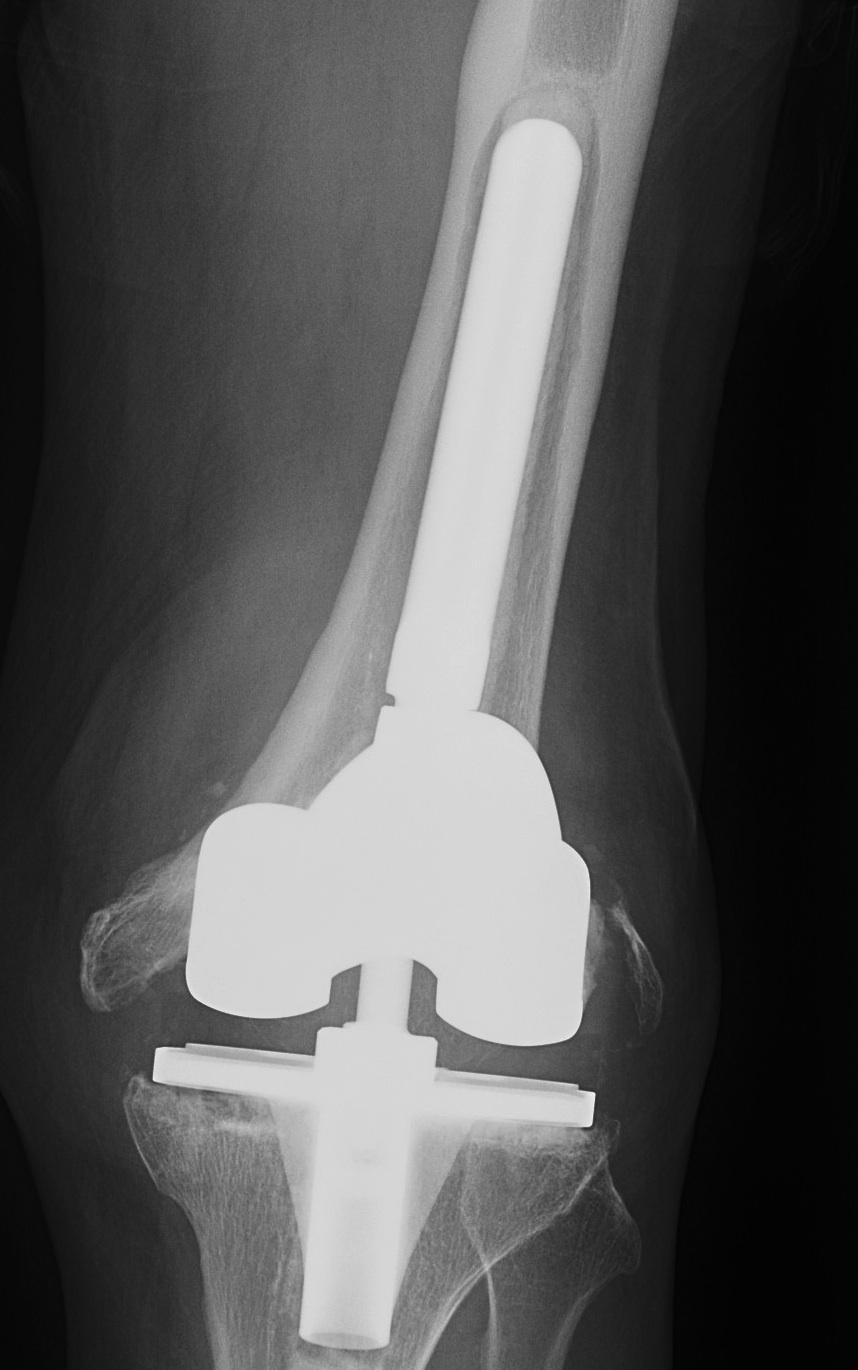

B. Tantalum cones metaphyseal filling / Trabecular metal

Meneghini et al JBJS Am 2009

- tantalum porous tibial implant in 15 pateints followed average 3 years

- AORI type 3 and type 2B

- knee society score average 85

- all had evidence osteointegration, no loosening

Howard et al JBJS Am 2011

- femoral tantalum components in 24 knees followed for averag 3 years

- knee society score average 81

- all well fixed with no complications